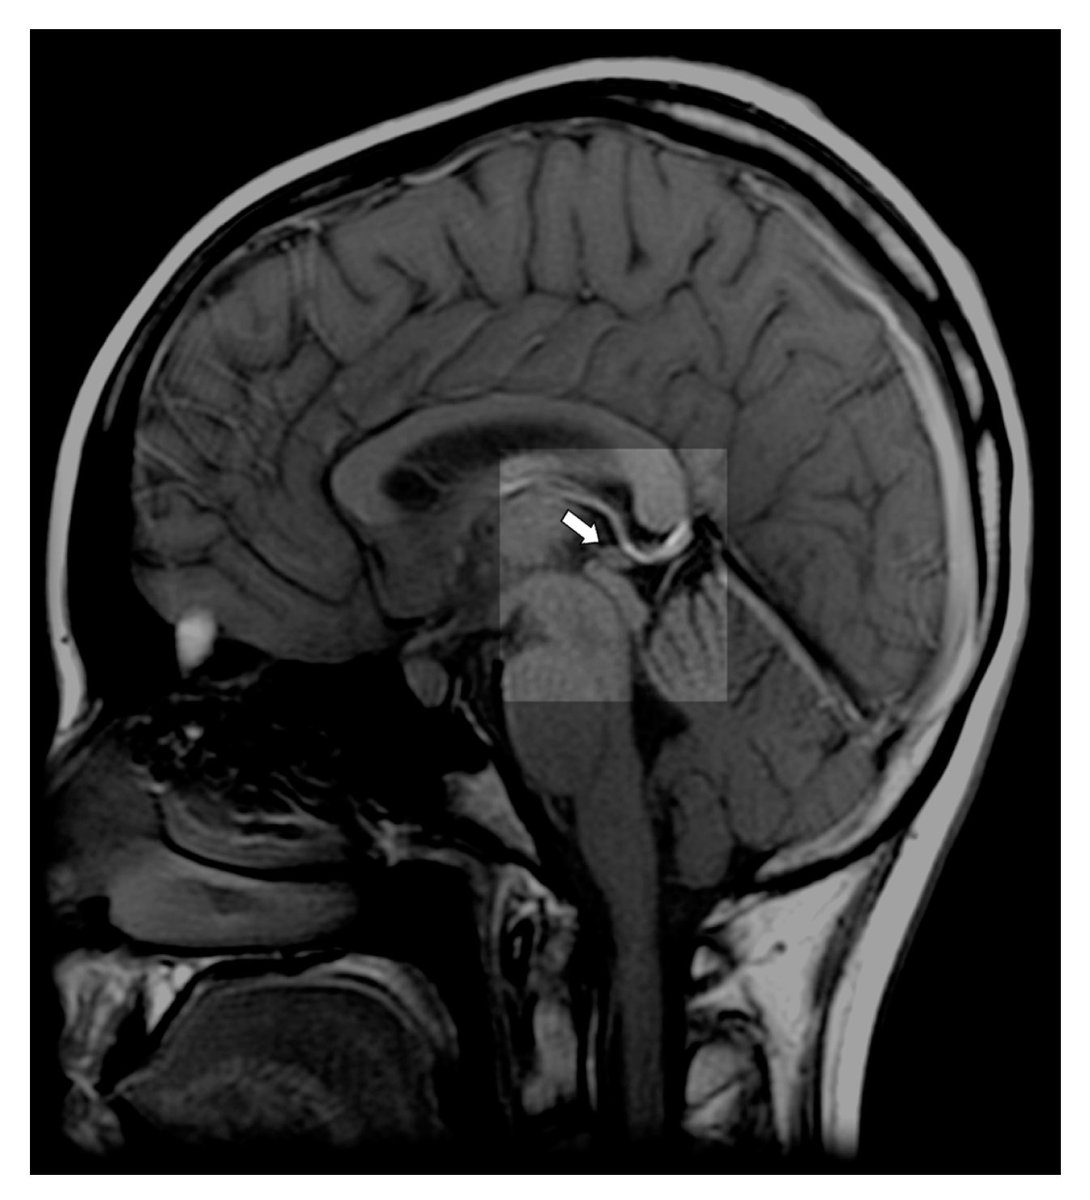

Шишковидной киста форум 115 фото